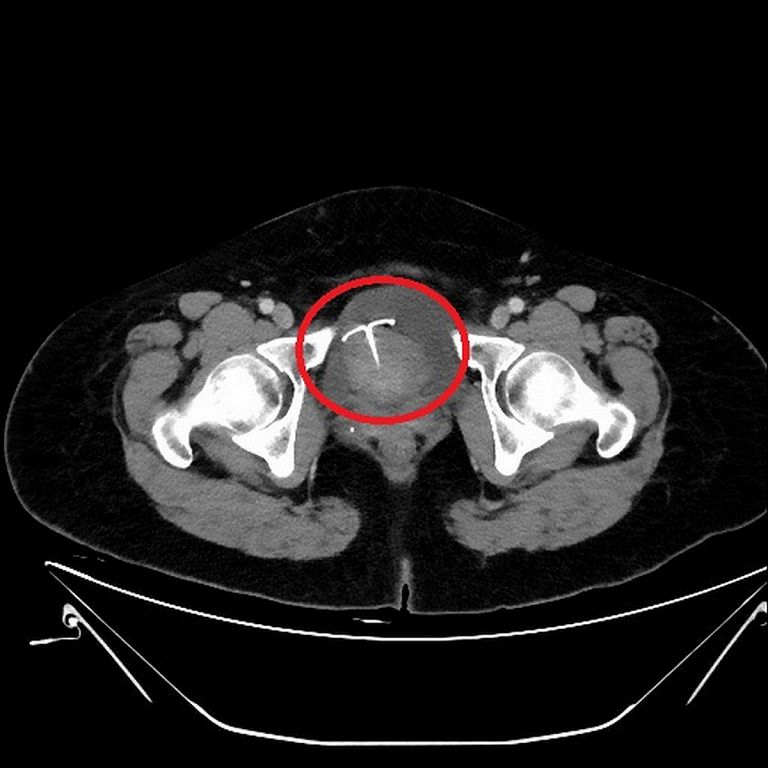

55歲的張女士日前因腹痛1個多月,本以為是腸胃症狀,至地方診所看診服藥後仍舊疼痛不止,遂至台北慈濟醫院婦產部門診就醫,經超音波檢查後發現竟是放置十餘年的銅製避孕器穿透子宮引起腹腔嚴重發炎感染且出現小腸沾黏,邱筱宸醫師以電腦斷層確認避孕器的確切位置後,執行子宮開腹切除術,將子宮摘除並仔細清理子宮及小腸的沾黏情況,術後病人恢復良好順利出院。

而根據統計,子宮內避孕器約有千分之8的機率會排出體外;甚至有千分之2的機率會穿破子宮掉入腹腔,導致腹痛、發炎,引發腸沾黏的問題發生。邱筱宸醫師表示,子宮避孕器會穿透子宮,並非裝設時的問題,而是避孕器對子宮來說是一種「異物」,無法完全貼合子宮的立體空間,所以身體會排斥它,因此避孕器容易透過子宮進入腹腔裡,掉出的避孕器若卡在患者膀胱,會產生血尿;掉進腹腔也可能引發化膿發炎,嚴重甚至會造成敗血症和腹膜炎。